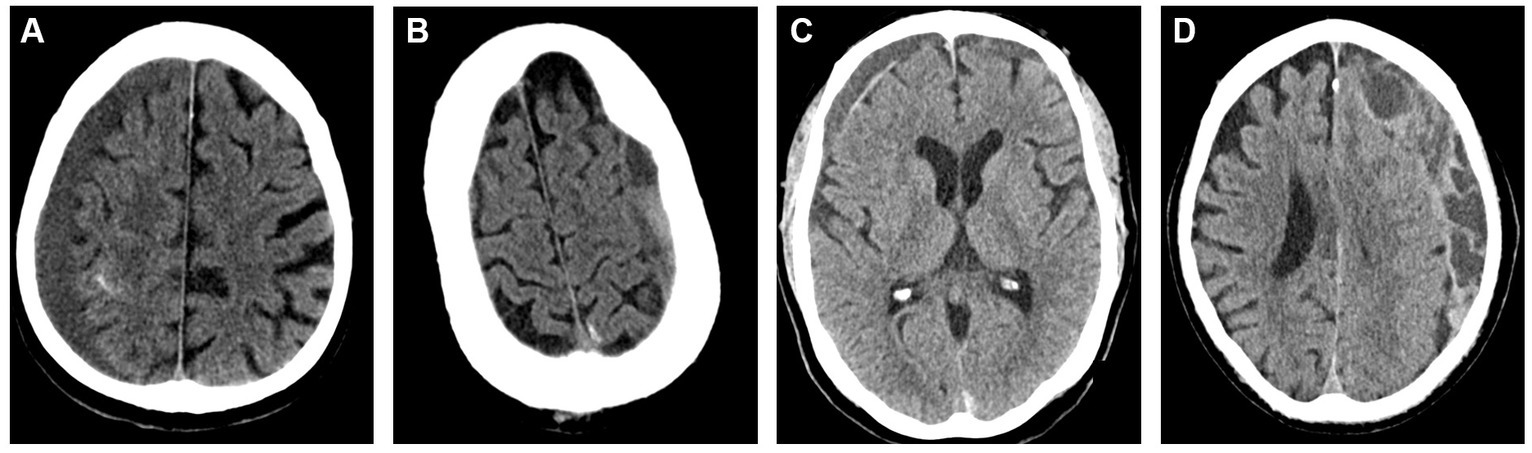

Figure 5

Representative images for cSDH subtypes based on the Nakaguchi classification system. Panel (A) – homogenous; Panel (B) – separated; Panel (C) – laminar, Panel (D) – trabeculated.

The heterogeneity of cSDH’s radiographic morphology has been extensively studied as a potential biomarker for disease recurrence. Multiple classification systems exist for characterizing the cSDH internal architecture. The most common scheme is the Nakaguchi classification system (26). In this study, cSDHs are categorized into four types–homogenous, laminar, separated, and trabecular. Homogenous and laminar (the early subtypes) are less likely to recur, while the separated hematoma (the later subtype) is more likely to recur after treatment. Data on outcomes following MMAE stratified by Nakaguchi cSDH subtypes corroborated these results, suggesting that the separate subtype was associated with slower hematoma resorption following MMAE. Trabecular subtypes were thought to be associated with resolving cSDHs with a low risk of recurrence. Representative images of the Nakaguchi classifications are presented in Figure 5. In a separate scheme, Nomura et al. (48) classified cSDHs by pattern of radiodensity (hyperdense, isodense, hypodense, mixed, or layered) and showed that the layered and mixed cSDHs were more likely to recur, while hypodense cSDHs were less likely to recur. Shimizu et al. (49) also demonstrated that gradation density hematomas are at higher risk of recurrence. More recently, Takei et al. (50) proposed modified criteria combining these classification systems into five subtypes—homogenous, gradation, laminar, separated, and trabecular—and showed that this modified system had higher interrater agreement than the Nakaguchi and Nomura classifications and that the gradation subtype was most strongly associated with cSDH recurrence. Research on radiographic predictors of cSDH recurrence remains an active area of investigation.